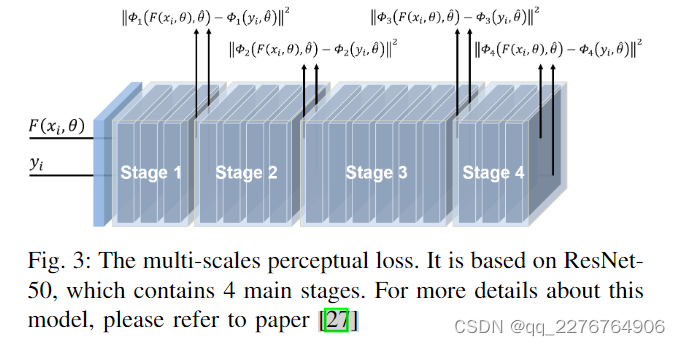

关于感知损失,如图3所示,我们利用ResNet-50[27]作为特征提取器来获得多尺度感知损失。 具体来说,我们丢弃模型末尾的池化层和全连接层,只保留模型前面的卷积层。 首先,我们首先加载在 ImageNet 数据集 [28] 上训练的模型权重,然后在训练过程中冻结这些权重。 在计算感知损失值时,去噪输出和目标图像都被发送到提取器进行前向传播(图3)。 我们选择ResNet的四个阶段之后的特征图,在每个阶段中图像的空间尺度将减半,代表不同尺度的特征空间。 然后我们使用 MSE 来衡量这些特征图的相似度。 通过对这些值进行平均来获得多尺度感知损失。